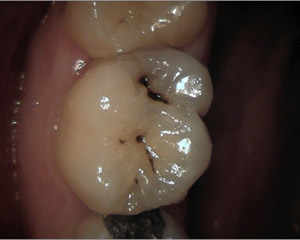

Normalment, amb la exploració clínica s'aprecien molts signes de malalties del pacient: càries, inflamació de genives, sagnat de genives, leucoplàsies, ulceracions, etcètera. Tot així, hi han moltes vegades que el diagnóstic no es pot realitzar, o aquest pot ser erroni si no es realitzen les proves complementàries adients. Al nostre centre disposem de potents càmeres intraorals que ens permeten identificar petites lesions de les dents (fisures, fractures, etc) que d'altre manera passarien desapercebudes.

caries1 caries2 caries3 caries4

A més, és molt important la realització de radiografies de dignòstic, tant a la primera visita com a les futures revisions, ja que el major nombre de les càries comencen als punts de contacte entre les dents o queixals, i aquests són innaccesibles visualment amb una exploració convencional.